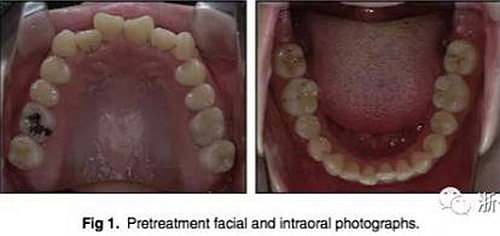

2.檢查:凸面型、骨性II類,安氏II類1分類錯合畸形。面型正中對稱,下面高略高,頦部后縮,唇肌略緊張。無顳下頜關(guān)節(jié)癥狀,下頜運(yùn)動正常,無偏斜。上下頜中線與面中線相一致,所有恒牙存在,口腔衛(wèi)生可,牙周情況可。患者健康,無系統(tǒng)性疾病,無牙科創(chuàng)傷史及不良習(xí)慣,懷疑遺傳因素導(dǎo)致錯合畸形。

3.測量分析:治療前記錄提示該患者左右磨牙與尖牙為安氏II類關(guān)系,上頜牙弓重度擁擠,下頜牙弓輕度擁擠,深Spee曲線。6.3mm深覆蓋,80%深覆合。牙齒無齲,無第三磨牙。

頭側(cè)分析提示為骨性安氏II類(ANB,8.4°;Wits,3.6mm),高角(SN-MP,44.9°),上頜切牙略舌傾(U1-SN,96.2°),下頜切牙略舌傾(IMPA,88。3°)(圖2;表)